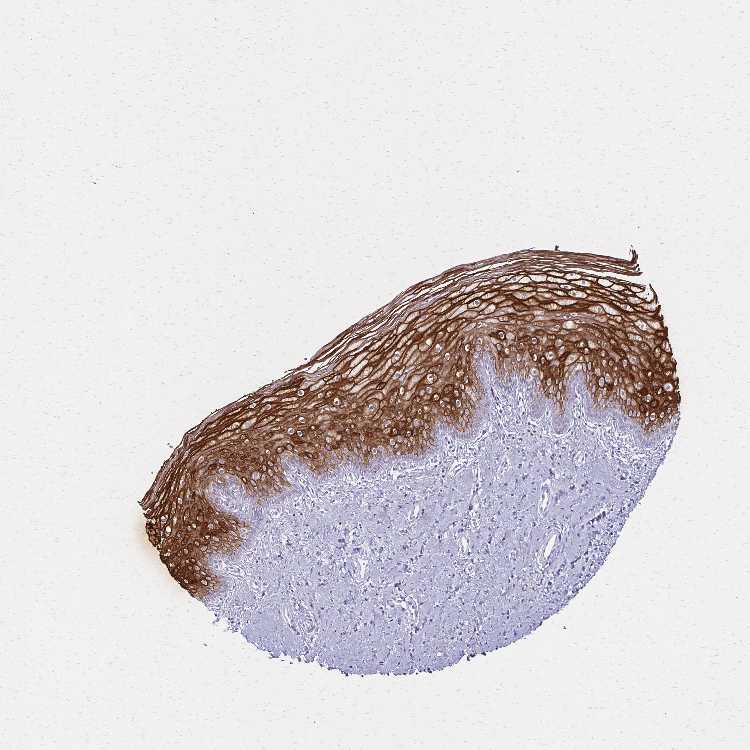

VAGINA - Antibody stainingi

Antibody staining in the annotated cell types in the current human tissue is reported as not detected, low, medium, or high, based on conventional immunohistochemistry profiling in selected tissues. This score is based on the combination of the staining intensity and fraction of stained cells.

Each image is clickable and will lead to virtual microscopy that enables deeper exploration of all samples and also displays staining intensity scores, fraction scores and subcellular localization as well as patient and tissue information for each sample.

Antibody CAB037321

Squamous epithelial cells High